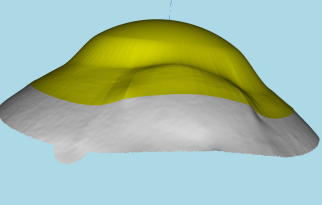

Scleral lenses are large diameter gas-permeable contact lens devices.

Rather than sitting directly on the eye like a traditional soft lens, scleral lenses only touch the sclera (the white part of the eye) and vault entirely over the cornea (the front of your eye - a clear layer of tissue that covers your iris, pupil and lens). This vault - the space between the contact lens and your cornea - is filled with fluid and creates a new, perfect focusing surface.